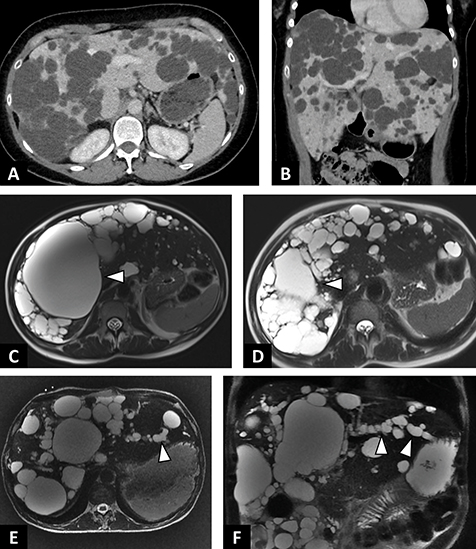

![]() |

| A–B : Polykystose hépatique non compliquée. A. Scanner abdominal en coupe axiale après injection de produit de contraste au temps portal. Multiples kystes hépatiques hypodenses, bien limités intéressant l’ensemble des segments hépatiques. B. Même scanner, reconstruc tion coronale. Augmentation en volume du foie conséquences des multiples kystes biliaires.

C–D : Polykystose hépatique chez une patiente symptomatique de 44 ans. C. IRM en séquence axiale T2 sans saturation du signal de la graisse. Kyste prédominant du foie droit (tête de flèche). D. IRM en séquence axiale T2. Contrôle 3 mois après alcoolisation percutanée du kyste prédominant. E–F : Polykystose hépatique chez un patient de 54 ans révélée par un ictère non fébrile. E. IRM en séquence axiale T2 avec saturation du signal de la graisse. Polykystose hépatique avec multiples kystes périhilaires comprimant le hile hépatique associé à une dilatation des voies biliaires d’amont (tête de flèche). F. IRM en séquence coronale T2 avec saturation du signal de la graisse. Dilatation des voies biliaires intra hépatiques du lobe gauche (tête de flèche). |